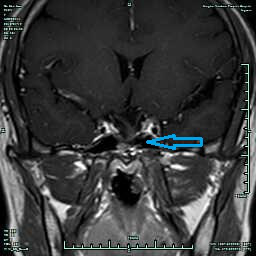

CASE2 病人***女性,46岁,因“视物明显下降2周”入院,入院诊断:垂体侵袭性大腺瘤;

在全麻下行经鼻内镜下垂体瘤切除,术后视力较前明显好转,术后恢复良好, 术后8天出院,出院3月复查仅海绵窦区少许肿瘤残留,继续随访。(红箭头提示垂体大腺瘤,蓝箭头提示术后复查海绵窦有少许肿瘤残留)